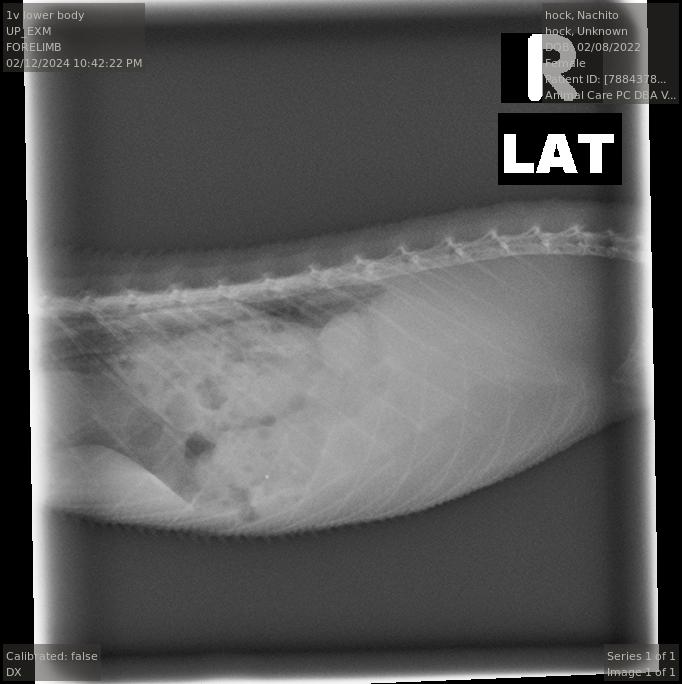

Also we got some ultrasounds and a xray to check on if she was truly still gravid. I'll post the x ray below.

Left is towards the head and RIght is towards the tail for the radiograph.